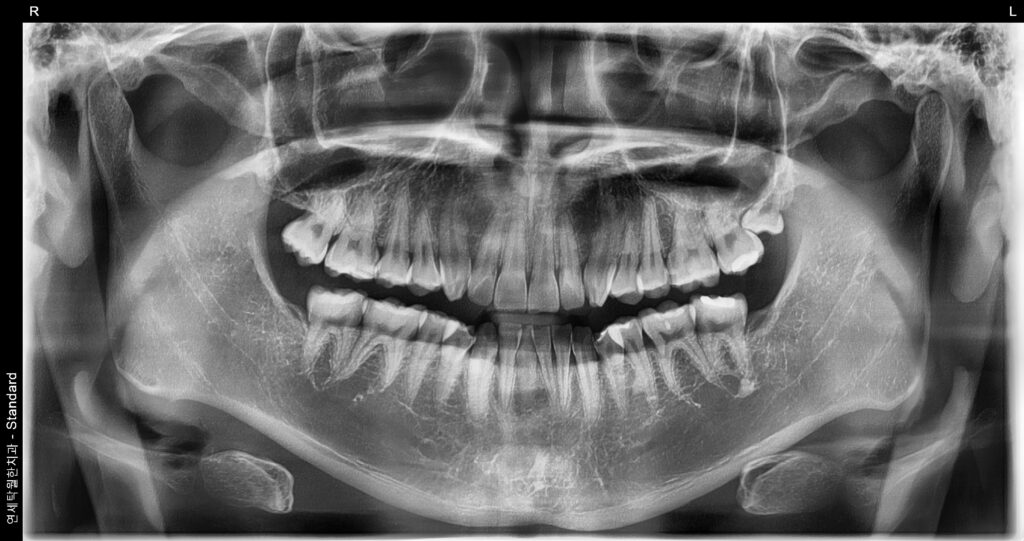

[원장칼럼]왼쪽 위에 사랑니가 났는데 금방 뽑히나요?

“왼쪽 위에 사랑니가 났는데 금방 뽑히나요?” 안녕하세요! 청주 연세탁월한치과 대표원장 이경탁 입니다. 양치질을 하다가, 혹은 혀로 입안을 훑다가 우연히 왼쪽